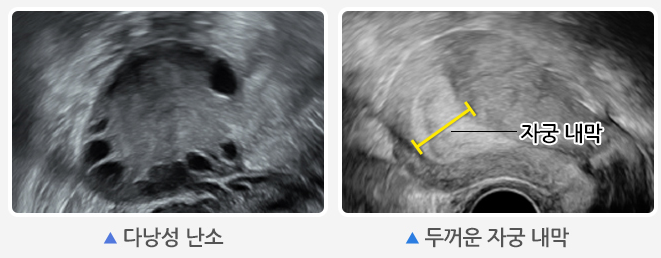

초음파 검사

난소에 작은 난포(2~9mm)가 12개 이상 보이거나 난소의 부피가 10㎤ 이상인 경우